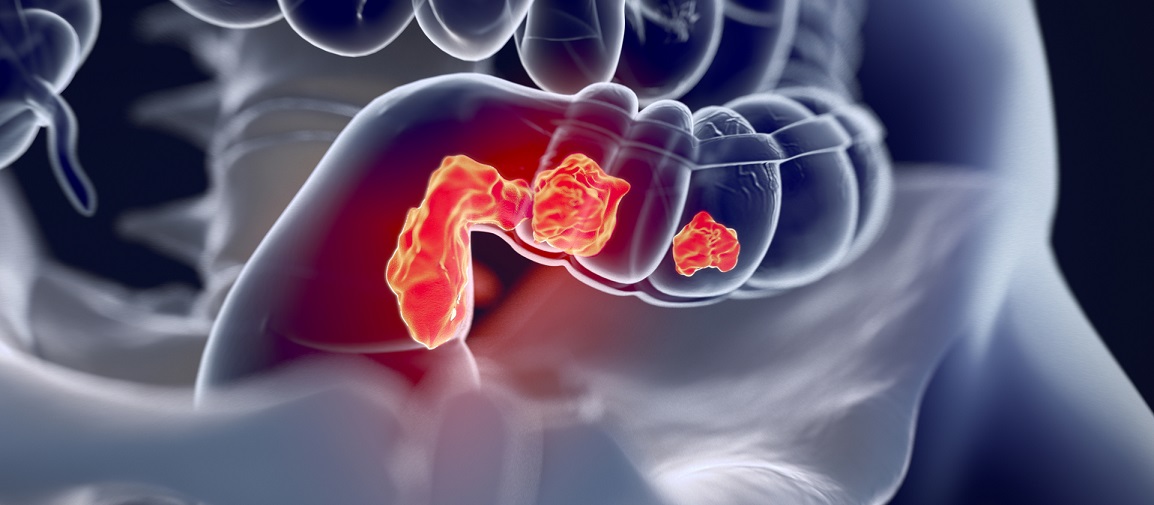

Σχηματική απεικόνιση του ορθικού καρκίνου